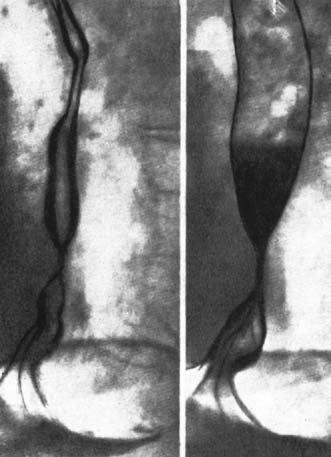

Послеожоговые стриктуры обычно циркулярные – трубчатые или кольцевидные, реже мембранозные, клапанные. Просвет органа в области стриктуры резко сужен вплоть до полной облитерации, при этом определяется супрастенотическое расширение в виде конуса или чаши (рис. 27).

Контуры сужения бывают довольно гладкими, рельеф слизистой отсутствует, перистальтика обычно не выявляется. При наличии множественных стриктур вышележащая диагностируется легко, но мешает обнаружению нижележащих.

Рис. 27. Рентгенограмма пищевода при его послеожоговом рубцовом сужении . На снимке видны супрастенотическое расширение конической формы и протяженная стриктура средне– и нижнегрудного отделов пищевода.